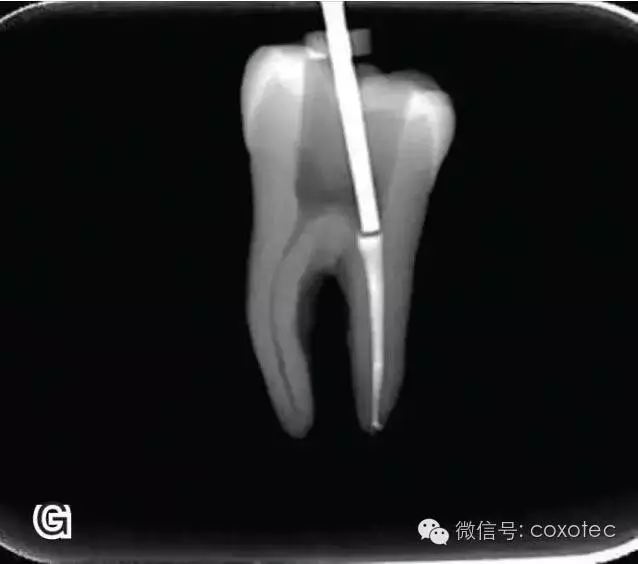

開(kāi)啟加熱器1秒鐘,迅速退出攜熱器工作尖,帶出中上段多余牙膠尖。用小號(hào)垂直加壓器向下加壓,完成根尖段的充填(圖7)。

圖7 退出攜熱器工作尖,A.垂直加壓器加壓 B.根尖段的充填完成